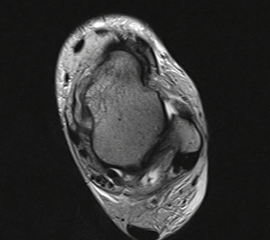

MRT

Die Kernspintomographie hat ihre Stärke in der Darstellung von Weichteilverletzungen. Insbesondere Verletzungen der Wachstumsfuge, des Periosts und der Bänder lassen sich gut visualisieren. Nachteilig ist die Untersuchungsdauer von 20-30 Minuten. Bleibt das Kind während dieser Zeit nicht ruhig liegen, kommt es zu Bewegungsartefakten, welche die Beurteilbarkeit der Bilder beeinträchtigen.

Mediale Malleolarfrakturen

Bei den medialen Malleolarfrakturen handelt es sich um Fugengelenkfrakturen bzw. Aitken II und III Verletzungen. Kennzeichnend ist, dass der Frakturverlauf die wachstumsaktive Zone zur Epiphyse hin durchkreuzt. Die Verletzung der wachstumsaktiven Zone macht diese Verletzungen besonders problematisch.

Fugengelenkfrakturen treten typischerweise vor dem 10. Lebensjahr auf, in einer Phase, in welcher die Wachstumsfugen noch weit offen sind. Dieser Frakturtyp betrifft fast ausschließlich den medialen Malleolus. Laterale Frakturen sind extrem selten, teilweise kommt es zu lateralen Bandverletzungen oder Fugenschaftfrakturen der distalen Fibula. Die Frakturlinie verläuft in einer Verlängerungslinie von der medialen Taluskante nach proximal. Häufig stellen sich Verletzungen des Innenknöchels im Röntgenbild schlechter dar, insbesondere wenn die Aufnahmen verdreht sind oder die Ebene der Fraktur bei geringer Dislokation verkippt zur Röntgenebene liegt. Besteht klinisch der geringste Hinweis auf eine Verletzung des Innenknöchels, muss aufgrund der Tragweite der Verletzung durch entsprechende Aufnahmen gegebenenfalls auch Schnittbildverfahren die Verletzung sicher diagnostiziert oder ausgeschlossen werden (Abb. 15).

„Kadiläsion“- Mediale Malleolarfraktur

Bei kindlichen Verletzungen des medialen Malleolus handelt es sich nach L. v. Laer um eine sogenannte Kadiläsion, d.h. eine Verletzung mit hohem Risiko eines schlechten Behandlungsergebnisses bei nicht korrekter Behandlung. Selbst bei optimaler Therapie ist das Risiko für spätere Wachstumsstörungen hoch, sodass diese Verletzungen nicht selten ein juristisches Nachspiel haben. Durch die Verletzung der wachstumsaktiven Zone kann es zu einem vorzeitigen Verschluss der Wachstumsfuge kommen, mit entsprechendem Fehlwachstum. Das Risiko eines vorzeitigen Verschlusses der Wachstumsfuge korreliert mit dem Ausmaß der Schädigung der wachstumsaktiven Zone. Ab dem 13. Lebensjahr wird das Risiko bei reduzierter Wachstumsaktivität zunehmend geringer.

Fugengelenkfrakturen können die Wachstumsfuge durchkreuzen (Abbildung 16a), ohne oder nur mit minimaler Beteiligung der Fuge sehr weit medial liegen (Abbildung 16b) oder durch die Fuge auslaufen (Abbildung 16c). Relevant für die Wachstumsprognose ist weniger die Form der Fraktur, sondern das Alter des Patienten zum Zeitpunkt des Traumas sowie das Ausmaß der Schädigung der Wachstumsfuge, wobei eine Korrelation mit dem Ausmaß der Dislokation besteht.